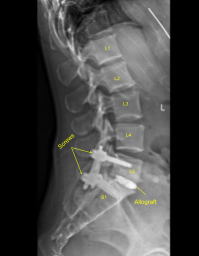

El autoinjerto morselizado seleccionado durante la descompresión, así como el aloinjerto morselizado, se canalizó hacia el interespacio con embudo y tamp, y luego el espaciador intersomático de titanio se apisonó suavemente en el interespacio bajo guía fluoroscópica y se expandió a la posición adecuada. La PA y la fluoroscopia lateral mostraron un posicionamiento apropiado.

A continuación, se obtuvo una tomografía computarizada adicional que muestra una posición ligeramente medial del alambre guía L5 izquierdo. Por lo tanto, la navegación Jamshidi se utilizó nuevamente para volver a canular el pedículo izquierdo L5 en una posición óptima. los tornillos pediculares navegados canulados se colocaron sobre los cables K y los cables K se retiraron con L5 y S1 izquierdos logrando una instrumentación no segmentaria.

Las capas dérmicas se cerraron con suturas Vicryl 2-0. Las incisiones de la piel se cerraron con suturas subcuticulares Monocryl 4-0, se limpiaron, se secaron estérilmente y se vistieron con pegamento Dermabond. El Dermabond también se aplicó para las incisiones del pasador Schanz de la matriz de cresta ilíaca. Obtuvimos una tomografía computarizada final y radiografías finales que muestran el posicionamiento correcto de todo el hardware.